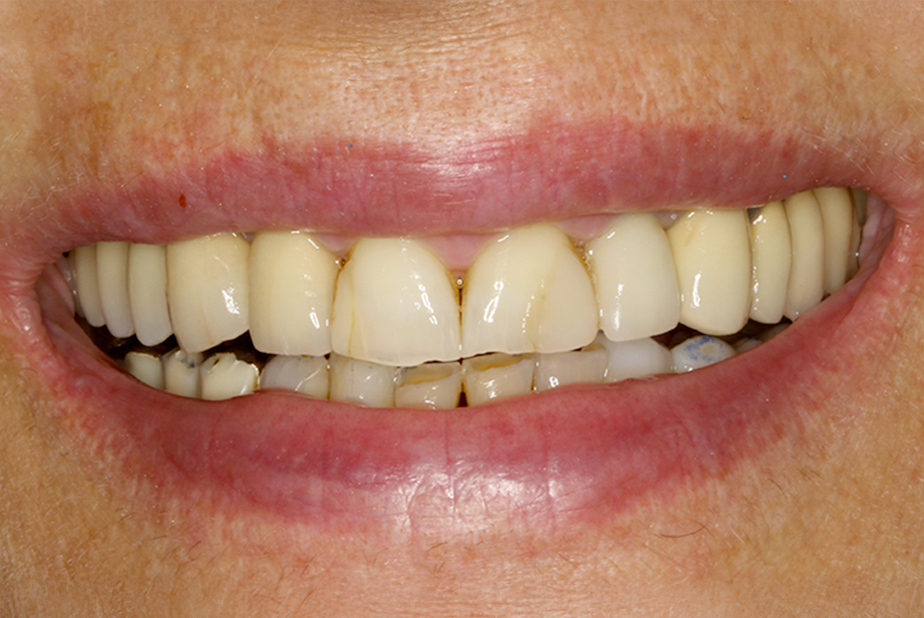

La finalizzazione del caso avveniva con protesi in metallo-ceramica passivata su cappe conometriche in bocca (Figs. 24, 25, 26, 27, 28, 29, 30, 31, 32) e radiografie finali ad un anno dal carico (Figs. 33, 34).

Applicazione ponte 17-14 in metallo ceramica su cappette conometriche passivate in bocca mediante cemento

Fig. 24 - Applicazione ponte in metallo ceramica su cappette conometriche passivate in bocca mediante cemento Multilink Hybrid e risultato finale

Applicazione ponte 17 - 14 in metallo ceramica su cappette conometriche passivate in bocca mediante cemento Multilink Hybrid e risultato finale

Fig. 25 - Applicazione ponte 17 - 14 in metallo ceramica su cappette conometriche passivate in bocca mediante cemento Multilink Hybrid e risultato finale